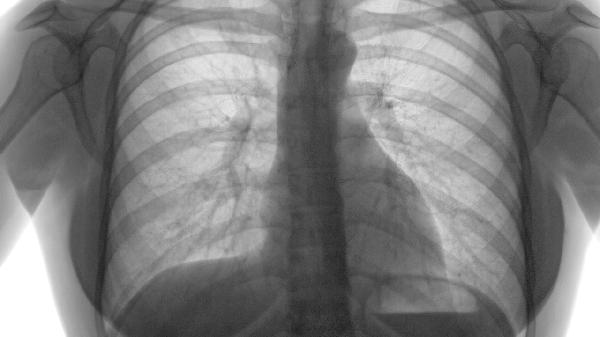

双肺肺气肿是怎么回事

双肺肺气肿可能由长期吸烟、空气污染、职业粉尘暴露、遗传性抗胰蛋白酶缺乏、慢性支气管炎等原因引起,可通过戒烟、氧疗、支气管扩张剂、肺康复训练、手术治疗等方式改善。建议及时就医,在医生指导下进行针对性干预。